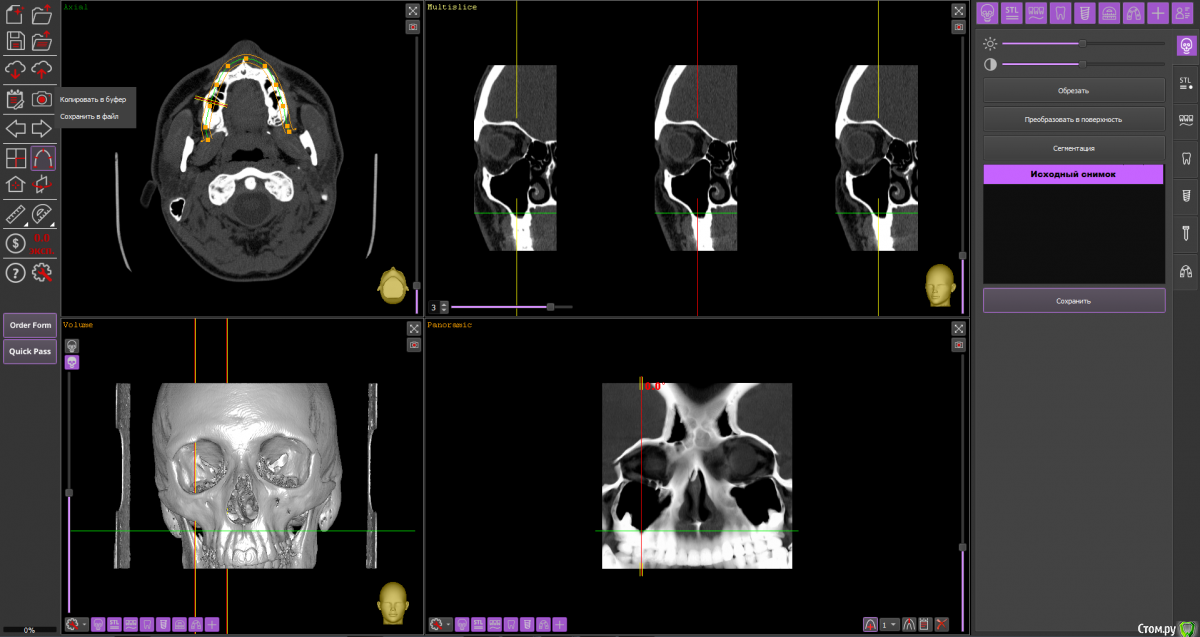

Dmitriytd Опубликовано 19 августа, 2020 Поделиться Опубликовано 19 августа, 2020 Здравствуйте, пожалуйста, посмотрите КТ( сделано в стоматологической клинике). Беспокоят проблемы с носом(постоянные прозрачные выделения, боли в пазухах, особенно при наклоне головы вниз). Знакомый лор посоветовал проверить на одонтогенный гайморит и я вспомнил, что делал КТ два года назад.Ссылка на КТ:https://yadi.sk/d/64pLNRildrWt5A Ссылка на комментарий

Dmitriytd Опубликовано 11 сентября, 2020 Автор Поделиться Опубликовано 11 сентября, 2020 Два года -кт не актуаленЗдравствуйте, сделал новое КТ. Пожалуйста, посмотрите:https://yadi.sk/d/1sbzO9z0QrurZg Ссылка на комментарий

wladdX Опубликовано 11 сентября, 2020 Поделиться Опубликовано 11 сентября, 2020 На мой взгляд, ничего примечательного в верхнечелюстных синусах нет. 1 Ссылка на комментарий